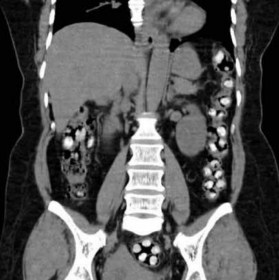

InternalHere’s the background. Knowing he was going to be arrested, Davis tried to smuggle in codeine and benzodiazepines for some other prisoners. Corrections knew he had drugs inside him because they’d been monitoring phone calls from these prisoners asking Davis to bring in some ‘candy’ when he turned himself in.

Once he was taken to prison, Corrections put Davis in a special ‘dry’ cell for ‘At Risk’ prisoners. These cells don’t have toilets. When the inmate wants to ‘go’, he is given a cardboard potty and is watched while he defecates. Once he’s done, prison officers look though the faeces to see what came out.  Corrections put Davis in one of these observation cells so they could catch him with the drugs and charge him with smuggling in contraband.